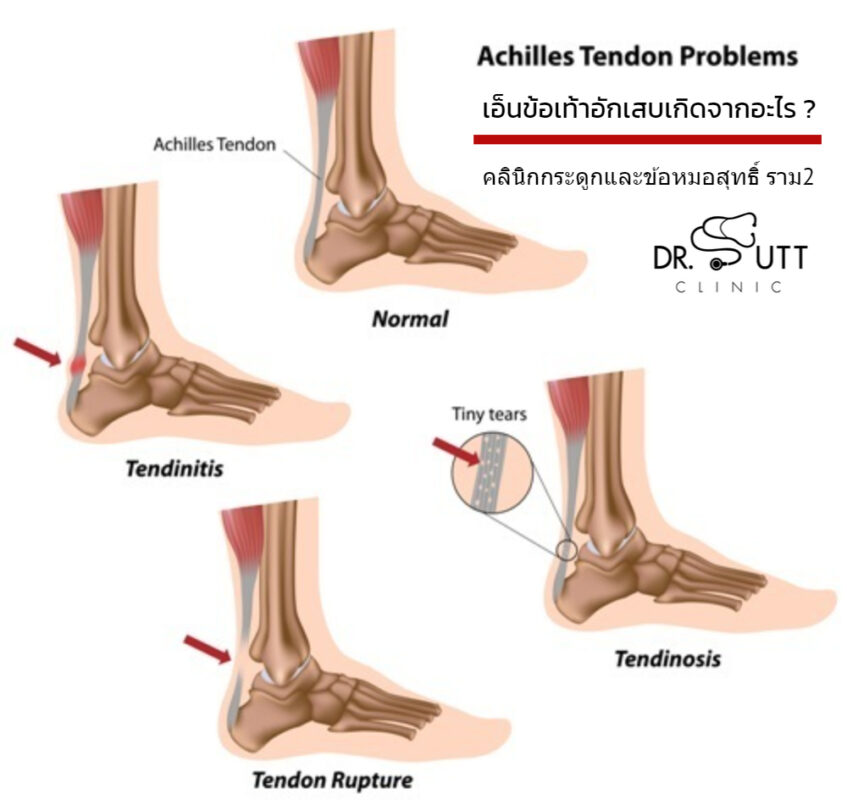

เอ็นข้อเท้าอักเสบเกิดจากอะไร ? – คลินิกกระดูกและข้อ (หมอสุทธิ์) องค์ประกอบ Png เท้าเล็ก ๆ สีม่วงการ์ตูน ดาวน์โหลดรูปภาพ (รหัส …